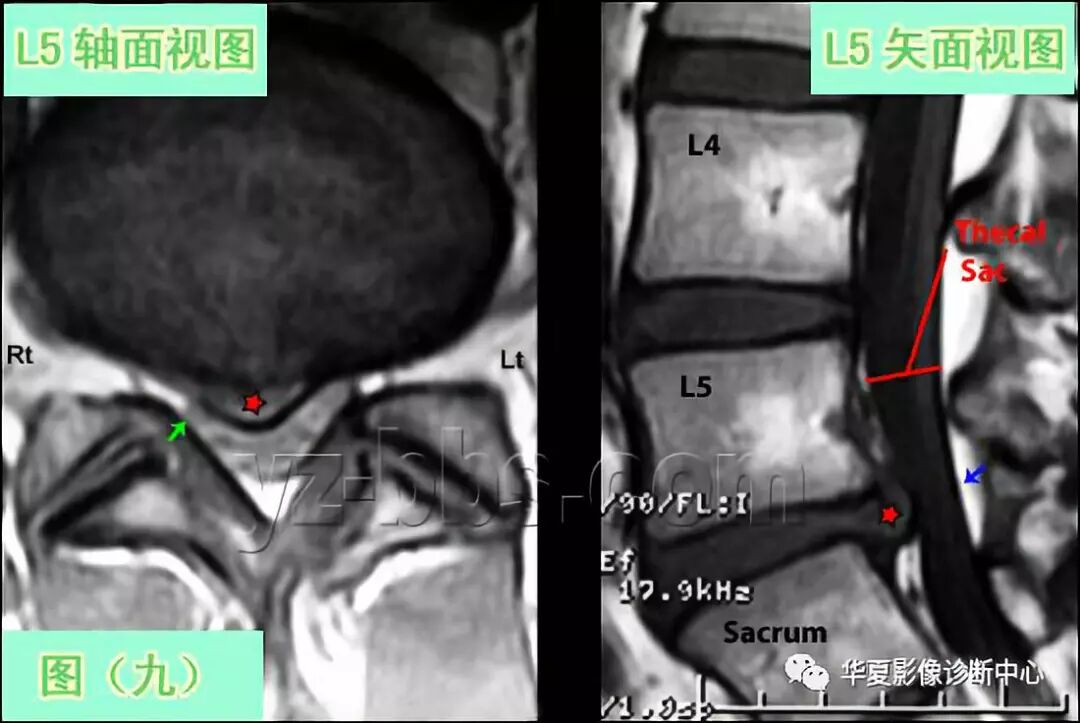

图(9)展示的是一个大的9mm的突出(红星)的T1轴状面及矢状面图

突出物已经完全将右侧过往神经根S1(图像左侧)遮盖掉(看不到),并将其挤压到椎板(小绿箭头)。

在轴状面及矢状面图(蓝箭头与红五星之间)可观察到硬膜囊有来自这个大的突出的中重度压迫。